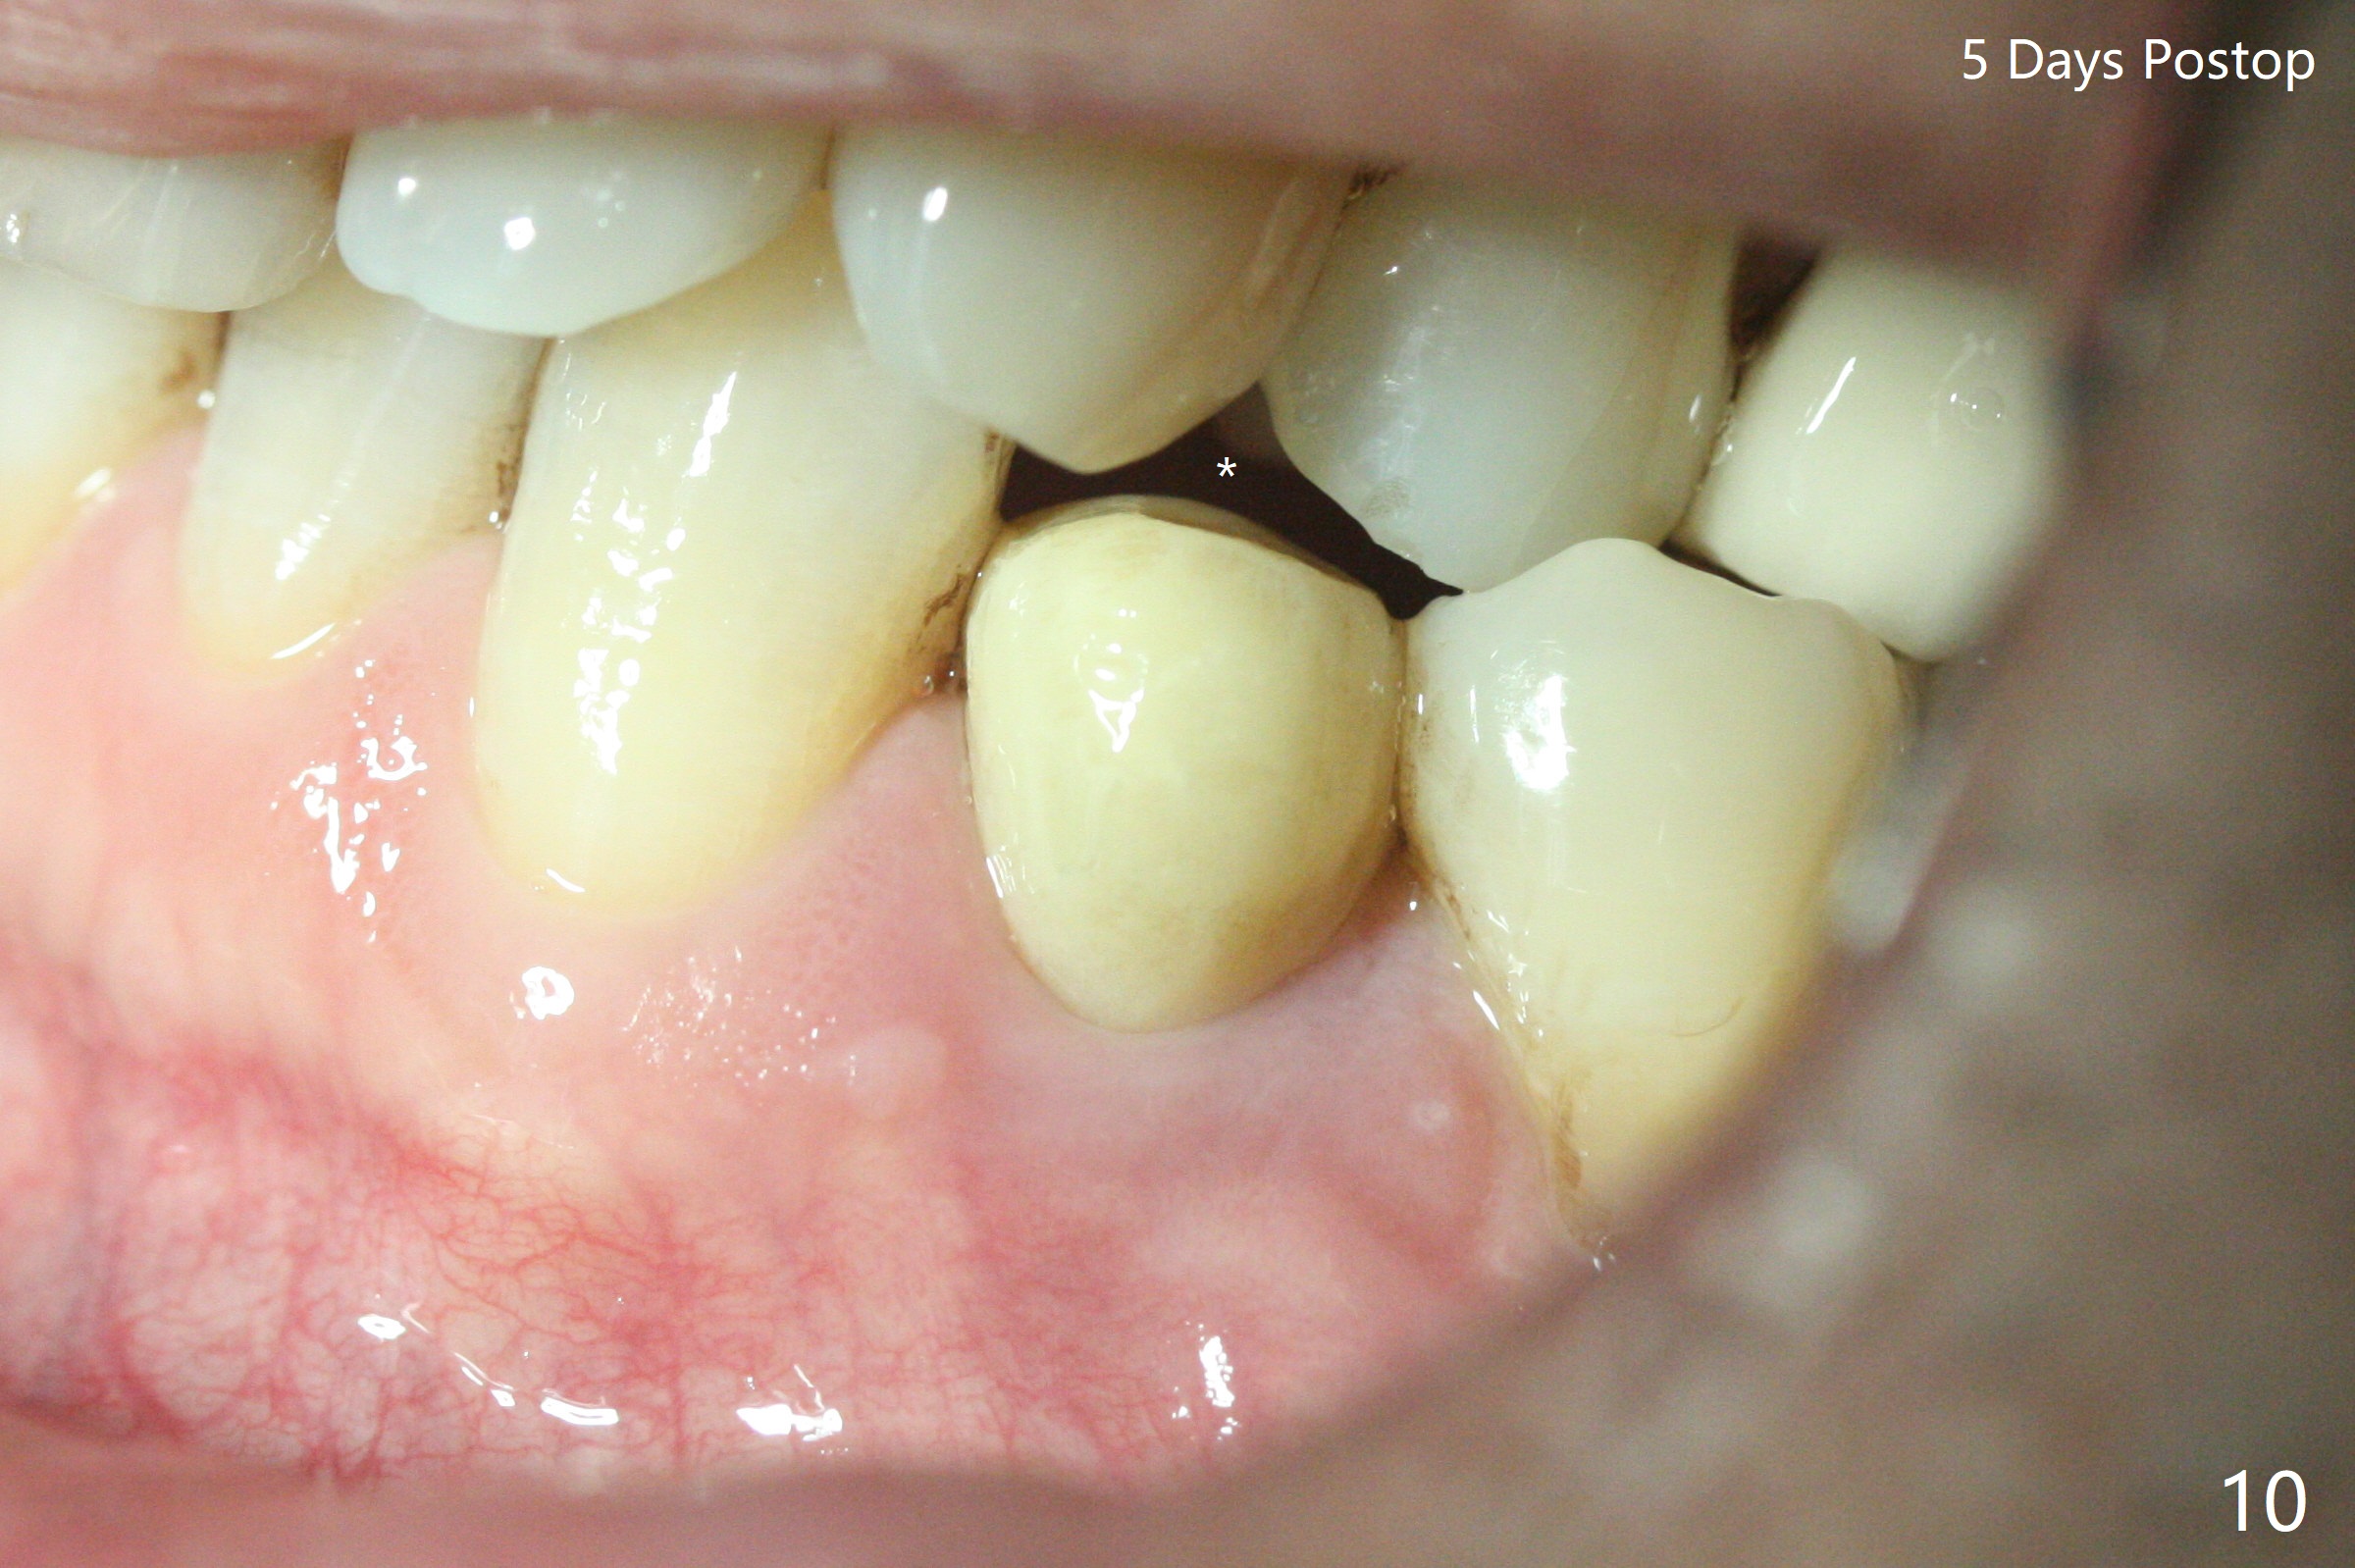

Three months post guide fabrication (coronavirus outbreak), the patient with loose post/crown returns for #21 extraction and immediate implant with guide (Fig.1 (*: post space)). In fact the root stump is flattened with diamond bur and 9 mm bone trimmer with guide before point drill. When the osteotomy finishes with 3.5x13 mm drill (under drilling with 10.5 mm offset), it has deviated buccal (Fig.2, 3,4); the outline of the bone trimmer mark is labeled by arrowheads in Fig.2. It appears that the center of the bone trimmer is dictated by that of the post space, as compared to Fig.1 *). When the root is removed except buccal shield (assuming that the deviation was due to the uneven surface of the root stump), the osteotomy is redone with guide, but remains buccal. Finally with buccal shield removal, a new lingual osteotomy is created free hand for a 4.5x11 mm implant (Fig.5) with 2-3 mm buccal gap for bone graft (Fig.6 * (literally)). In brief, bone trimmer also deviates according to resistance, basically irrelevant to the guide sleeve. The immediate provisional is intentionally removed 5 days postop to check whether a piece of gauze is retained in the socket as a gingival retraction cord for temporary crown fabrication; the buccal gap is kept with bone graft (Fig.7 *). No foreign body is in place. The margin of the abutment seems quite subgingival (Fig.8 *), but re-trimmed and polished provisional looks harmonious with the surrounding gingiva and the opposing dentition (Fig.9,10). The patient returns for prophy 2 months postop; the immediate provisional is removed for trimming and polishing. The bone graft seems to be integrated into a part of the gingiva (Fig.11 >). The abutment cuff appears to be too short.